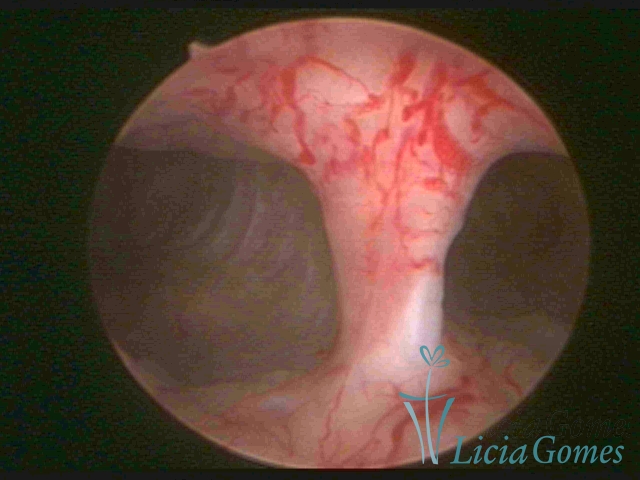

Bicornuate uterus

Malformation in which there is the lack of the flat portion of uterine fundus due to the lack of fusion on the proximal portion of paramesonephric ducts. The uterine fundus has two narrowed spaces in a divergent oblique angulation. It may be complete, from the fundus to the cervix; or partial, completely dividing the uterine cavity.

The tilted uterus which presents the most difficult hysteroscopic diagnosis occurs when there is only a small indentation of the uterine fundus.